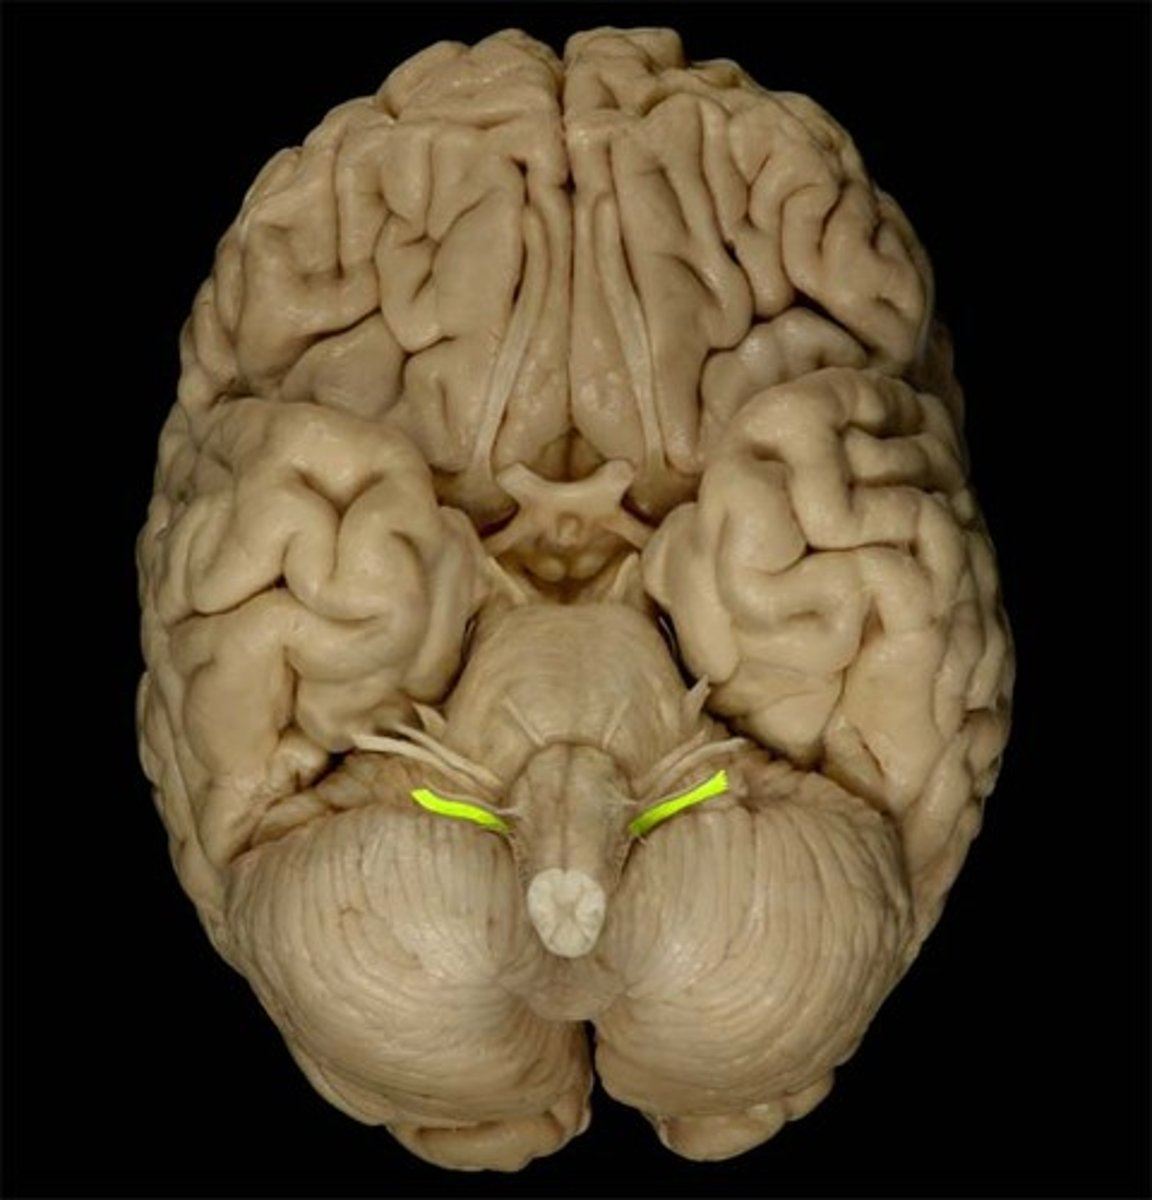

IV Trochlear

motor eye movement